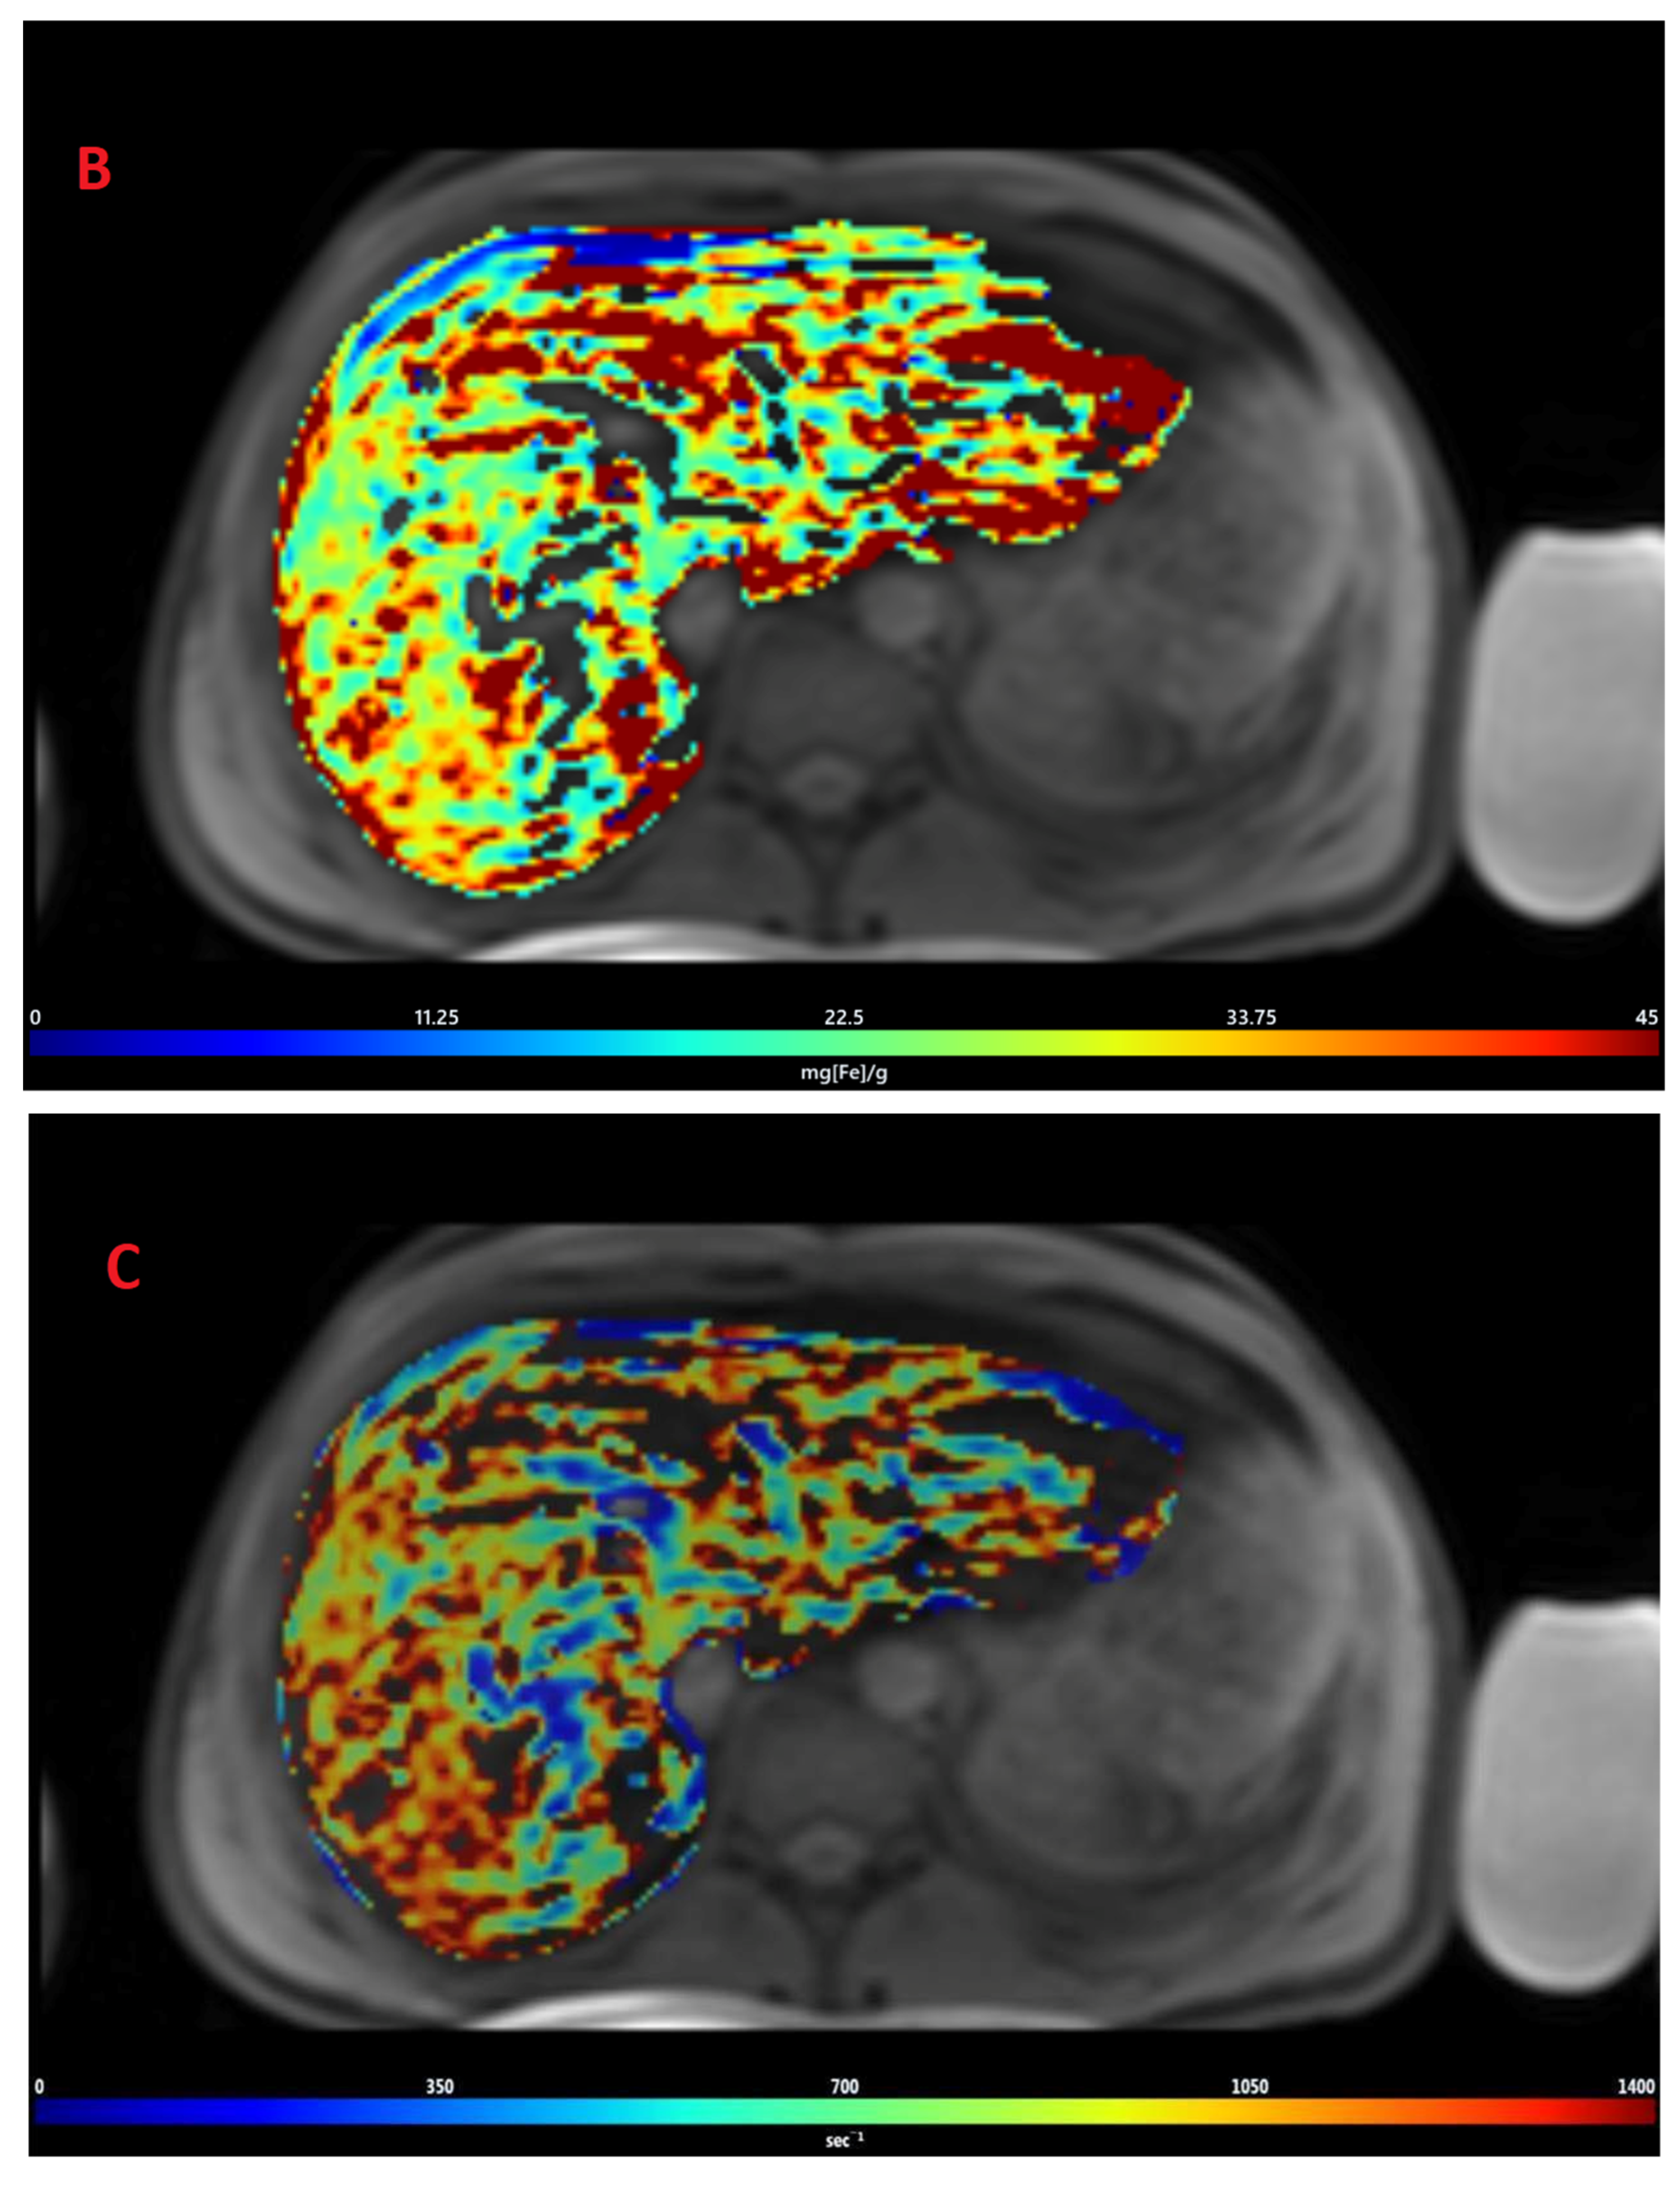

3.1. Estimation of LIC by R2 Relaxometry (LIC R2)

3.2. Estimation of LIC by R2* Relaxometry (LIC R2*)